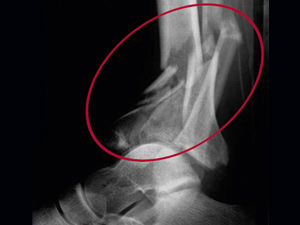

2. FRACTURAS POR FLEXIÓN

1. fuerza actúa en dirección perpendicular al eje mayor del hueso, en uno de sus extremos, estando el otro fijo.

1. elementos de la concavidad ósea están sometidos a compresión, mientras que la convexidad está sometidos a distracción

1. la línea neutra puede continuar en un trazo único o dividirse en la zona de concavidad, produciéndose la fractura en alas de mariposa.

2. FRACTURA POR CIZALLAMIENTO

1. Hueso sometido a una fuerza de dirección paralela y de sentido opuesto, originándose una fractura de trazo horizontal.

2. FRACTURA POR TORSIÓN

1. acción de dos fuerzas que rotan en sentido inverso. Se originaran las fracturas espiroideas